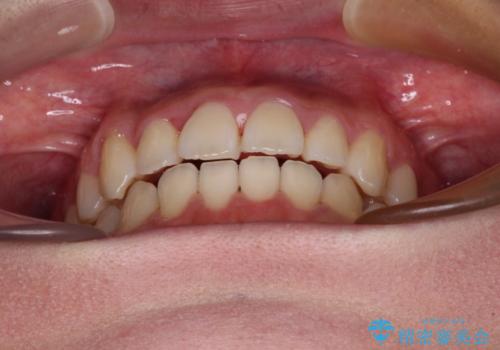

- 前歯の開咬と、上顎前歯の八重歯やデコボコを気にして来院された患者様です。

上顎歯列が狭窄していたため、急速拡大装置により上顎骨を側方に拡大し、その後ワイヤー装置にて矯正治療を行うこととしました。